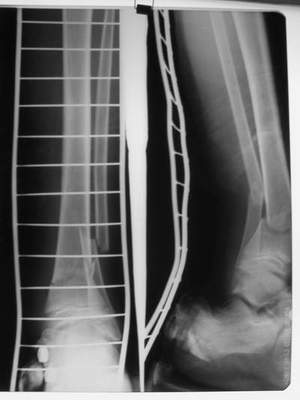

A> Перелом костей н\3 правой голени со смещением.

Это от 13.10.04? А это близкие к первичным снимки?

A> Перелом большеберцовой

A> кости можно охарактеризовать как компрессионно-оскольчатый.

A> В январе 2005: варусная деформация н\3 голени,

A> Операции: 1 Клиновидная резекция на вершине деформации м\берцовой кости.

A> 2 Тугоподвижный ложный сустав н\3 б\берцовой кости.

A>> Перелом костей н\3 правой голени со смещением.

AVM> Это от 13.10.04? А это близкие к первичным снимки?

Есть даже тень периостальной костной мозоли и сросшийся перелом

малоберцовой кости.

Это сросшийся перелом малоберцовой кости. И ложный сустав

н\3 б\берцовой кости.

Так как речь зашла непосредственно о травме, см этапные

снимки. Как все было

Первичные

Вытяжение

Фиксация

в гипсе

Промежуточный